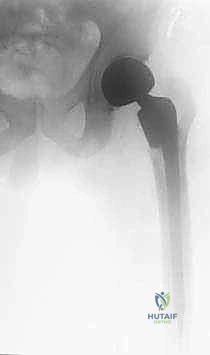

رأب نصف مفصل الورك هو إجراء جراحي دقيق يتم فيه إزالة رأس وعنق عظمة الفخذ المكسورين والتالفين، واستبدالهما بمفصل صناعي معدني متطور.

لماذا يُسمى "نصف" مفصل؟

لأنه يتم استبدال جزء واحد فقط من المفصل (وهو رأس الفخذ الكروي)، بينما يتم الاحتفاظ بتجويف الحُق الطبيعي (Socket) الخاص بالمريض كما هو دون تغييره. هذا يختلف عن "تغيير مفصل الورك الكامل" (Total Hip Replacement) الذي يتم فيه تغيير الرأس والتجويف معاً (والذي يُفضل عادة للشباب أو لمن يعانون من خشونة متقدمة في تجويف الحوض).

أنواع المفاصل الصناعية النصفية (Hemiarthroplasty Types)

هناك عدة أنواع من المفاصل النصفية، ويقوم الأستاذ الدكتور محمد هطيف باختيار النوع الأنسب بناءً على عمر المريض، مستوى نشاطه الحركي قبل الإصابة، وجودة عظامه.

1. من حيث التصميم (أحادي القطب مقابل ثنائي القطب)

- المفصل أحادي القطب (Unipolar): يتكون من قطعة واحدة صلبة (ساق معدنية متصلة برأس كروي كبير). الرأس الكروي يحتك مباشرة مع غضروف الحوض الطبيعي للمريض. يُستخدم عادة للمرضى الأقل نشاطاً.

- المفصل ثنائي القطب (Bipolar): تصميم أكثر تطوراً؛ يحتوي على رأس معدني صغير داخل رأس بلاستيكي (بولي إيثيلين) أكبر. هذا يسمح بالحركة داخل المفصل الصناعي نفسه، بالإضافة إلى الحركة بين المفصل الصناعي وتجويف الحوض. يقلل هذا التصميم من تآكل غضروف الحوض بمرور الوقت، ويوفر مدى حركياً أفضل واستقراراً أعلى لمنع الخلع. وهو الخيار المفضل للدكتور هطيف لمعظم مرضاه لضمان ديمومة أطول.